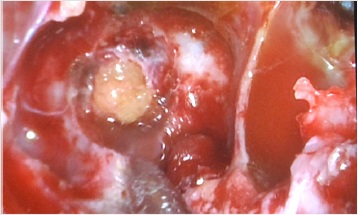

Before surgery, a lumbar puncture was performed to administer 0.25 mL of 10% fluorescein with 10mL of cerebrospinal fluid (CSF) to help visualize CSF leaks during surgery and to ensure there was no leak after reconstruction of the defect. The patient underwent endoscopic trans nasal transsphenoidal surgery. The anterior and middle portions of the clivus were exposed between both carotid arteries. During surgery, the defect was defined to the left of the midline in the clivus. The basilar artery was seen through the defect in prepontine cistern (Figure 2). The defect was closed with a multilayer reconstruction consisting of fat, fasciculata and naso septal flap (Figure 3). There was no recurrence of CSF leak at 2 years follow-up.

A 57-year-old man referred for clear watery discharge from the right nostril of no obvious cause. He suffered from intermittent rhinorrhea starting 6 months prior to arrival. He reported recent history of bacterial meningitis one month ago, which was treated successfully at an outside hospital. On admission, he had no focal neurological deficits. Nasal fluid tested positive for beta 2 transferrin. Brain MRI revealed that the right sphenoid sinus was filled with CSF (Figure 4). CT cisternography showed that the contrast material passed from the prepontine cistern into the sphenoid sinus through this bone defect in the clivus (Figure 4). After intrathecal administration of 0.25mL of 10% fluorescein with 10 mL of cerebrospinal fluid the patient underwent endoscopic trans nasal approach. After stripping the mucosa from posterior wall of sphenoid sinus, CSF leak was observed in the upper region of clivus just below the sella at the midline (Figure 5). The defect was closed by abdominal fat and reinforced by fasciculata and naso septal flap. At the During 30-month follow-up appointment, no signs of recurrence were found. In both above reviewed cases, a lumbar drain was not placed pre or postoperatively.